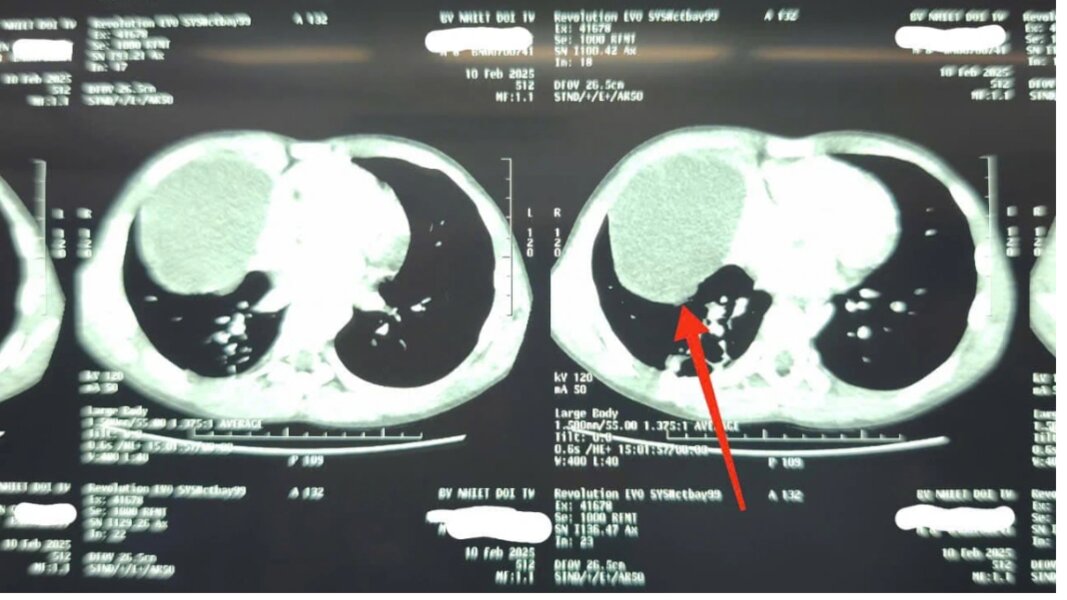

Tại khoa Nhi, kết quả kiểm tra khiến gia đình vô cùng bất ngờ. Cháu B đau vùng mạn sườn phải, khó thở nhẹ, hình ảnh X-quang cho thấy trắng xóa 1/2 dưới vùng ngực phải, siêu âm có tràn dịch màng phổi và có hình ảnh của nang dịch. Chụp cắt lớp vi tính phát hiện xẹp phổi dạng dải thùy dưới phổi phải, có nang dịch trung thất trước kích thước 72x80mm.

Bác sĩ Nguyễn Thành Lê, Phó Trưởng Khoa Nhi, Bệnh viện Bệnh Nhiệt đới Trung ương cho biết: "Thực tế, khối u nang dịch trung thất đã tồn tại từ trước nhưng chưa có triệu chứng. Cú ngã chỉ là sự trùng hợp về thời gian khi khối u nang bì vỡ, khiến triệu chứng trở nên rõ ràng hơn. Điều này có nghĩa là dù không bị ngã, bệnh của cháu vẫn sẽ tiến triển và gây nguy hiểm nếu không được phát hiện kịp thời”.